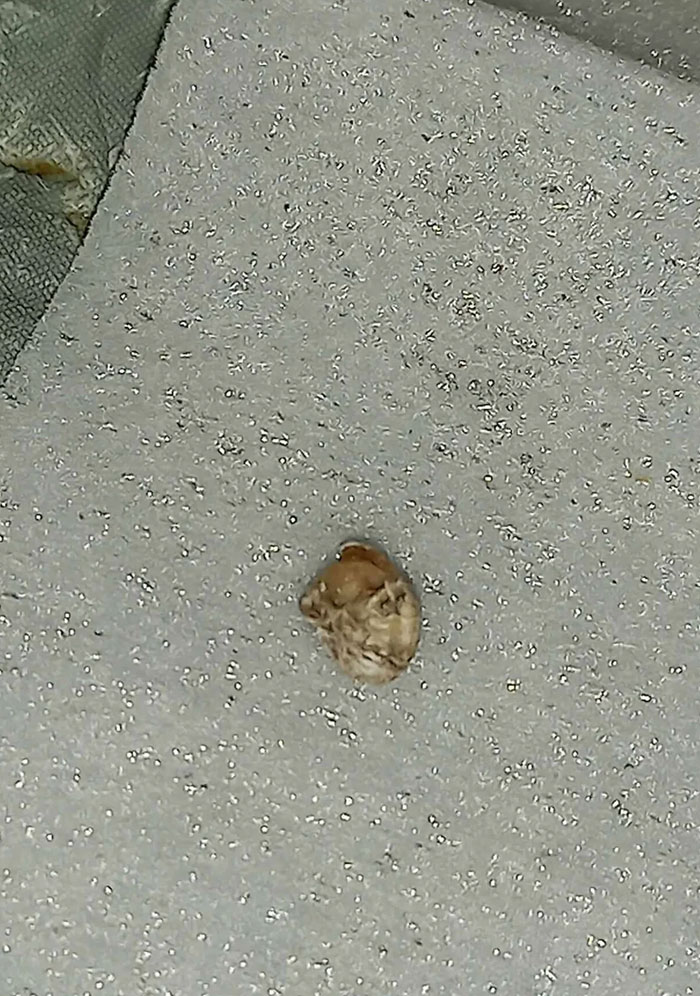

#76 Tonsil Stone That's Been Stuck For Weeks, Finally Got It Out

Image credits: yntaxx55